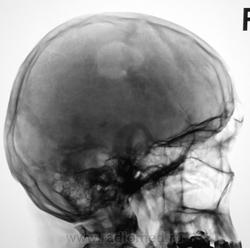

- https://radiomed.ru/sites/default/files/styles/case_slider_image/public/user/12/4.201311050033.jpg?itok=XHnjF6eB